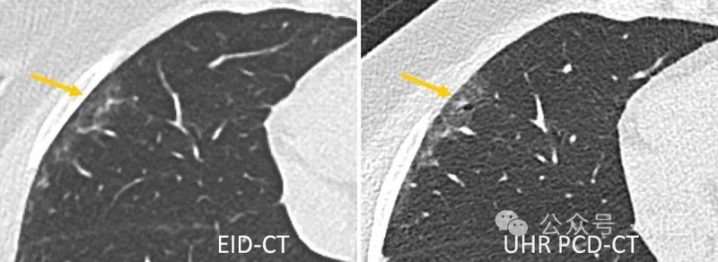

在高分辨率肺部成像中,与EID-CT相比,PCD-CT可提供更好的图像质量,而辐射剂量却明显更低。在一项针对30名因怀疑患有ILD而接受传统EID-CT和PCD-CT检查的患者的研究中,UHR PCD-CT在辐射剂量略低的情况下显示出明显更好的整体图像质量和清晰度。此外,UHR PCD-CT还提高了读者对是否存在网状结构、磨玻璃不透明和马赛克模式等成像结果的可信度,对是否存在通常的间质性肺炎的可信度也有了特异性的提高,参见图7中的示例。一项比较PCD-CT和EID-CT的模型研究证实,高分辨率PCD-CT能以较低的辐射剂量更准确地量化肺结节体积和气道壁厚度。

图7 通过第三代DSCT(左)和第一代PCD-DSCT(右)获得的间质性肺病患者的肺部扫描图。UHR PCD-CT扫描证实右肺中叶外围存在牵引性支气管扩张(箭头),并与轻度磨玻璃衰减相叠加。这一发现在EID-CT扫描中被忽略。